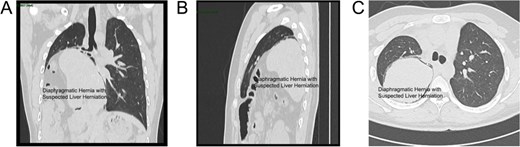

The patient was a 19-year-old male who experienced shortness of breath following physical activity 3 months earlier. Further examination identified a diaphragmatic hernia, and on 8 July 2024, he sought treatment in the Department of Thoracic Surgery at a hospital. Physical examination showed dullness to percussion in the right thoracic cavity from the second to sixth intercostal spaces, with an elevated liver dullness border. CT imaging confirmed a right-sided Bochdalek hernia with partial herniation of the liver into the thoracic cavity, compression, and atelectasis of the right lung, and mediastinal shift (Fig. 1). Upper gastrointestinal X-ray with contrast identified a filling defect in the duodenal bulb, mucosal irregularity, and proximal jejunum displacement in the upper right abdomen, suggestive of malrotation. A significantly elevated right hemidiaphragm further indicated the presence of a diaphragmatic hernia.

CT scan views of the thoracic hernia with suspected liver tissue involvement: (A) Axial view. (B) Frontal view. (C) Sagittal view.